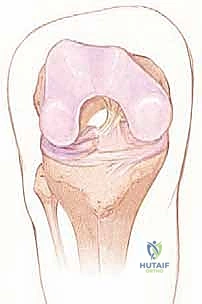

تُعد إصابة الرباط الصليبي الأمامي (Anterior Cruciate Ligament - ACL) من أكثر الإصابات الرياضية والحركية شيوعاً وتعقيداً في عالم جراحة العظام. الركبة ليست مجرد مفصل بسيط يعمل كفصلة باب، بل هي بنية حيوية معقدة تعتمد على تناغم دقيق بين العظام، الأربطة، الغضاريف، والعضلات. عندما يتمزق الرباط الصليبي الأمامي، ينهار هذا التناغم، وتفقد الركبة استقرارها الدوراني والانتقالي، مما يحول أبسط الأنشطة اليومية، ناهيك عن الرياضة الاحترافية، إلى تحدٍ محفوف بالألم والشعور بـ "خيانة الركبة" (Giving Way).

يقع الرباط الصليبي الأمامي في قلب مفصل الركبة، ويمتد بشكل مائل من الشق بين اللقمتين (Intercondylar notch) في عظم الفخذ، نزولاً إلى السطح العلوي لعظم الظنبوب (القصبة).